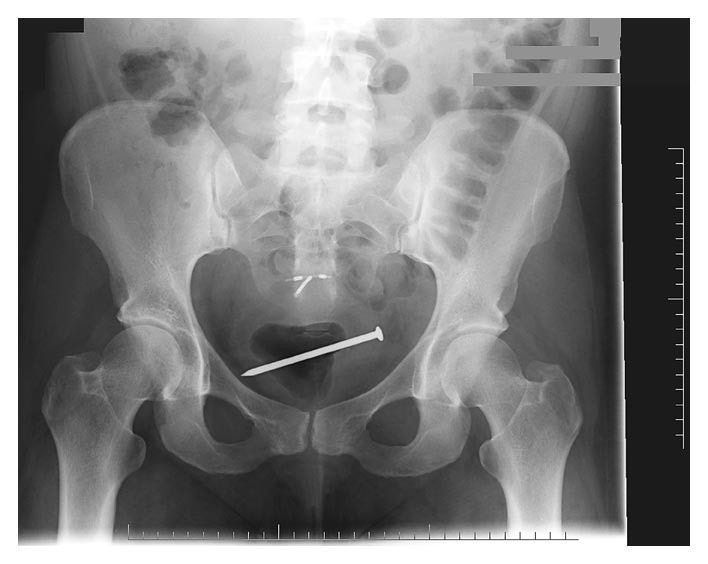

Figure 1. Гвоздь в полости мочевого пузыря. В полости матки визуализирована внутриматочная спираль.